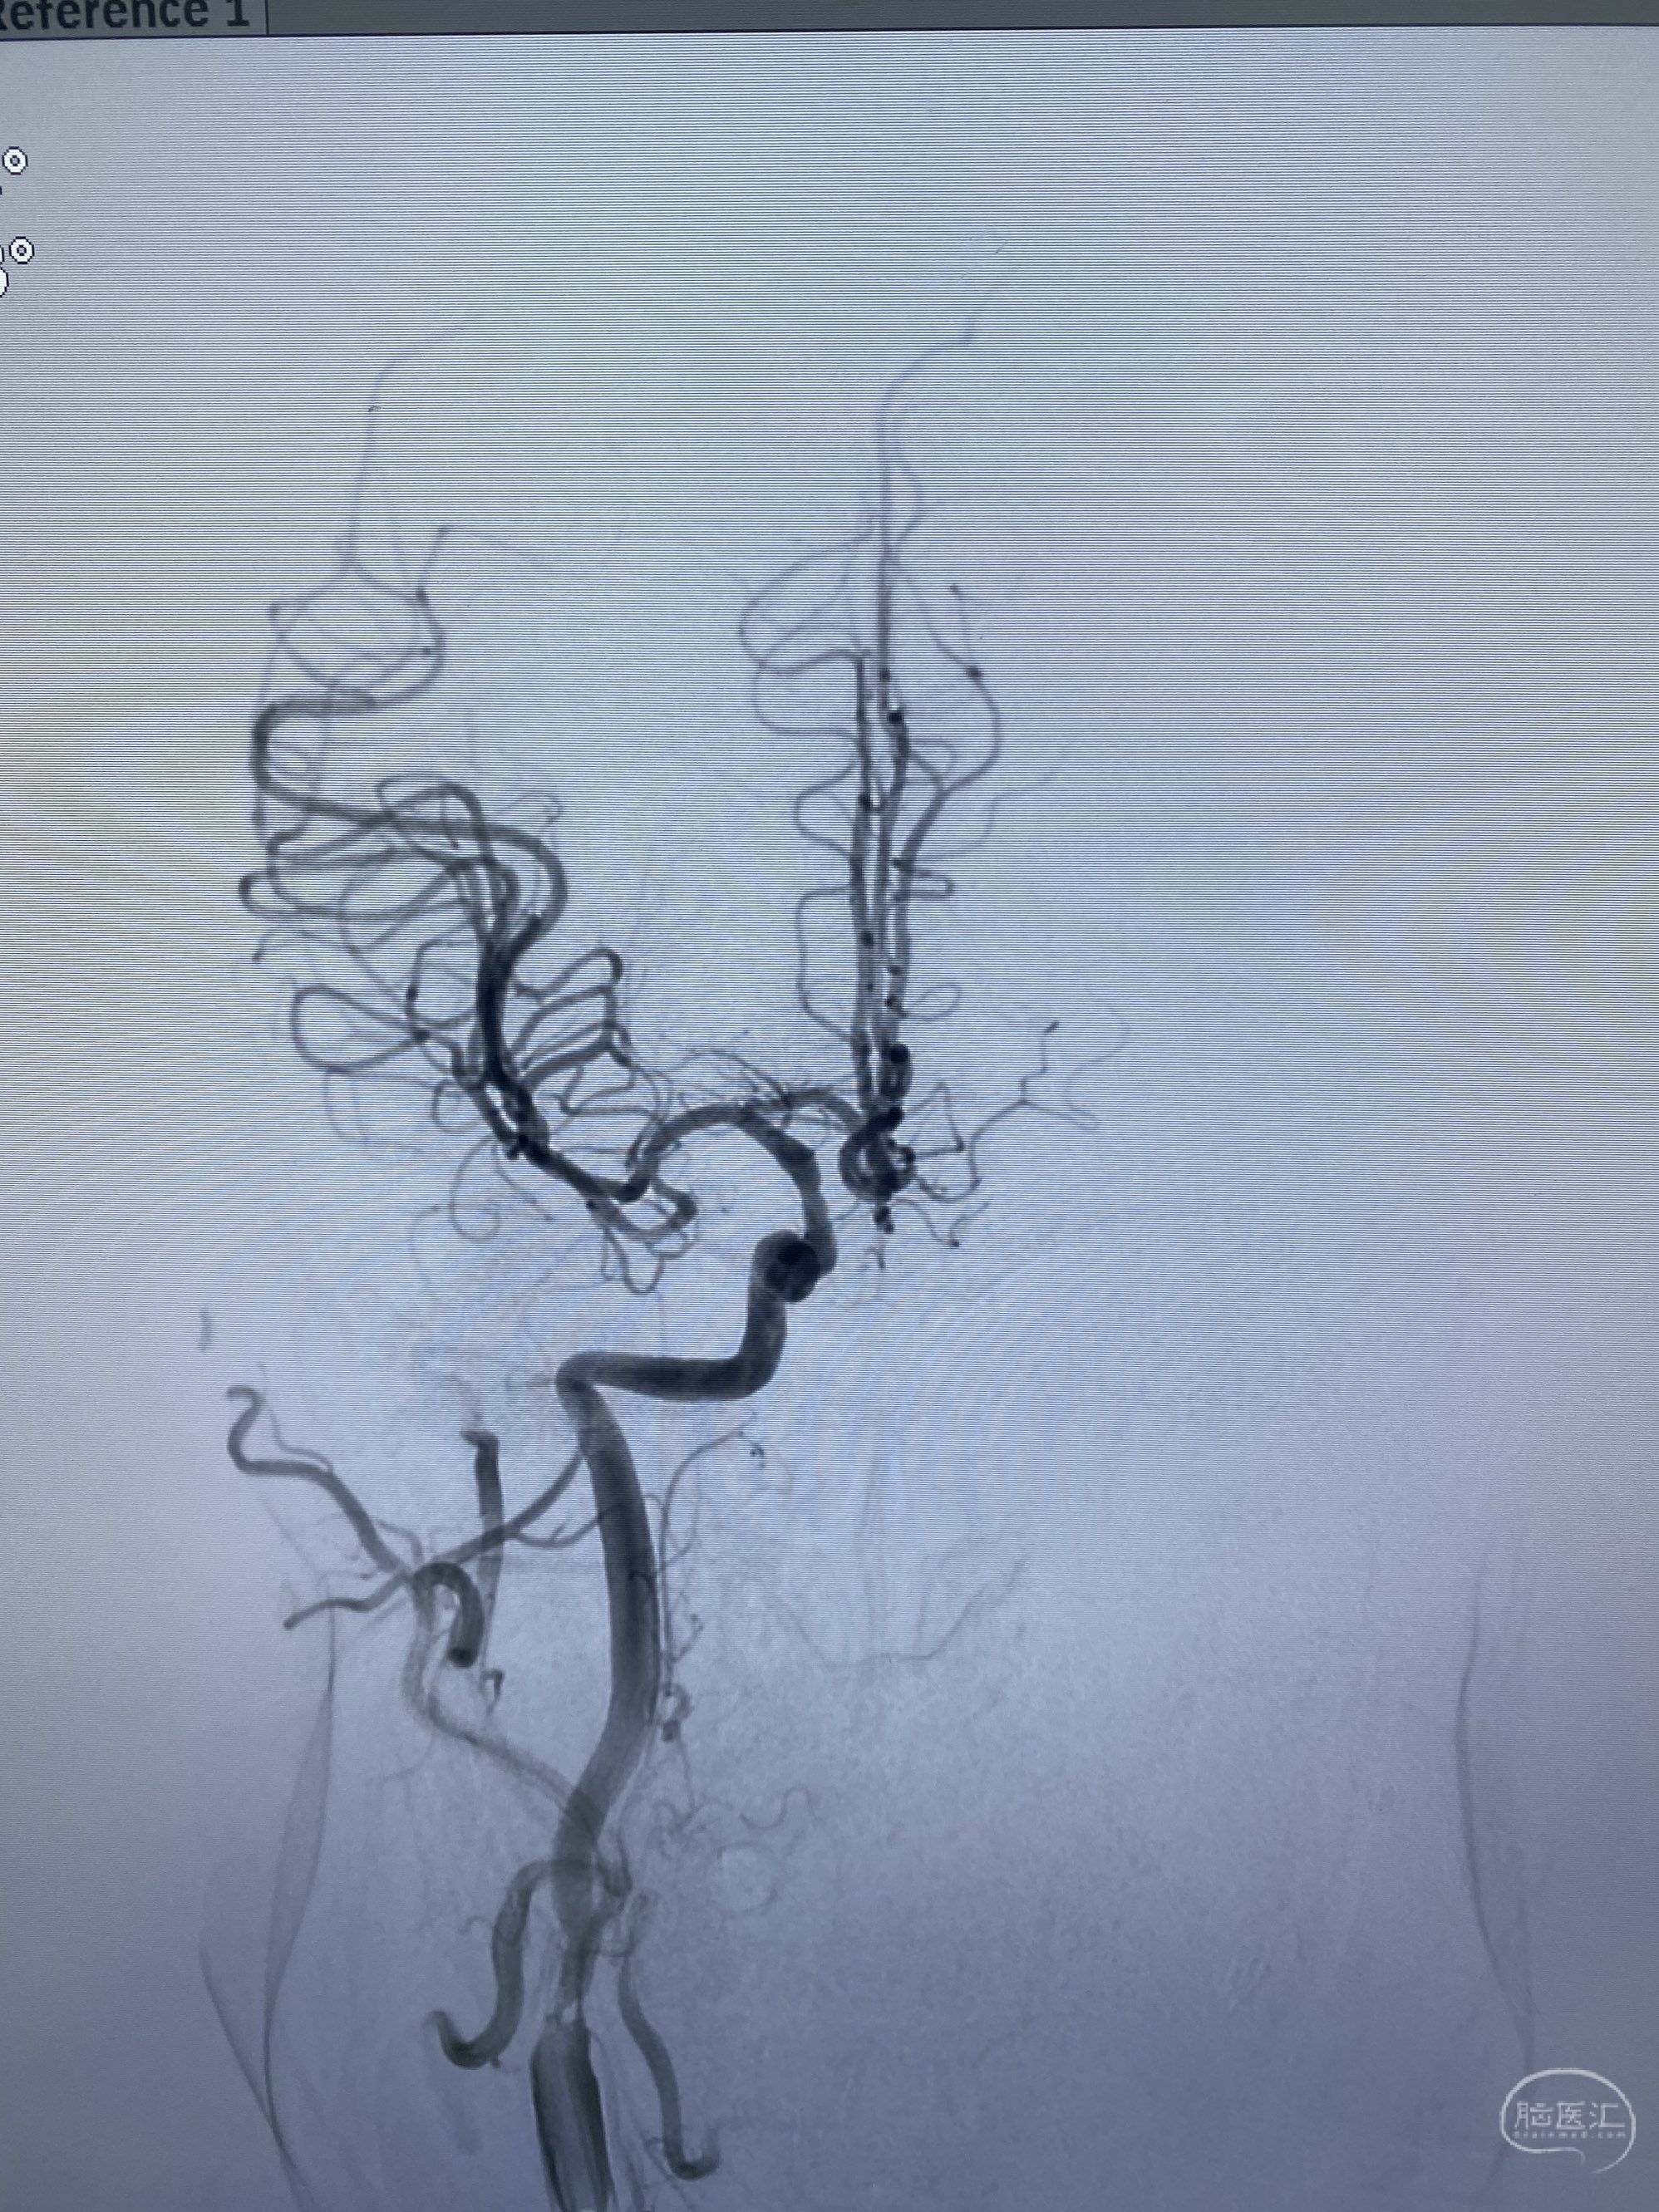

今日手术,TJG,M62Y,一期左侧颈动脉狭窄支架植入,二期椎动脉V4段多发夹层动脉瘤伴狭窄,常规支架辅助栓塞方法复杂又危险,血流导向装置植入快捷又安全。南阳市中心医院神经内科脑血管病介入团队pipeline flexFD植入两人导师资格。

椎动脉颅内段多发夹层动脉瘤伴载瘤动脉狭窄pipeline flex植入

今日手术,TJG,M62Y,一期左侧颈动脉狭窄支架植入,二期椎动脉V4段多发夹层动脉瘤伴狭窄,常规支架辅助栓塞方法复杂又危险,血流导向装置植入快捷又安全。南阳市中心医院神经内科脑血管病介入团队pipeline flexFD植入两人导师资格。